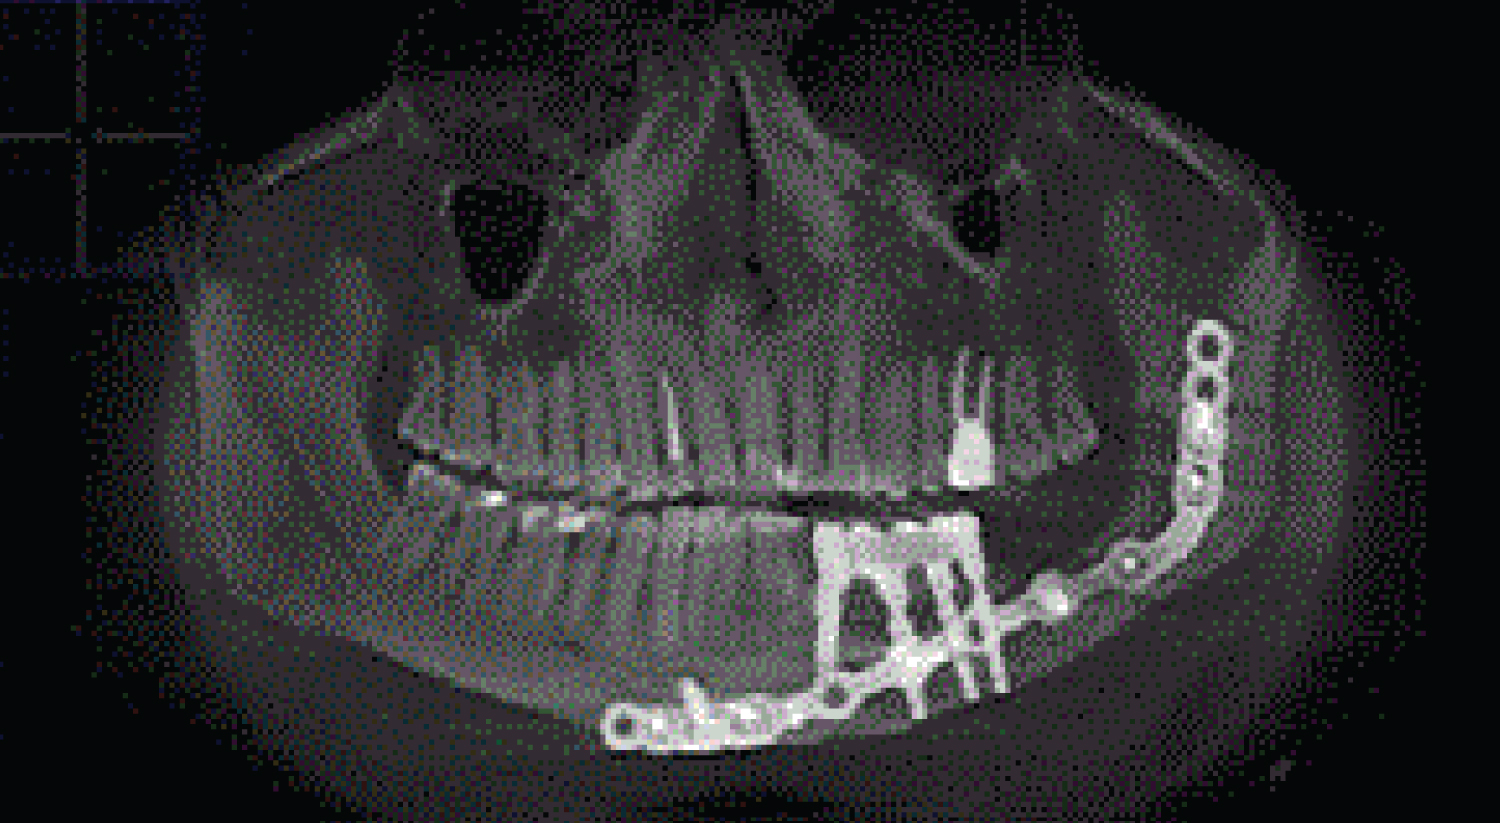

To assess the degree of osseointegration and determine the timing of the functional load of dental implants installed in free vascularized bone autografts, a Resonance-Frequency Analysis (RFA) of the stability of implants using Osstell Mentor (Osstell instrument, Integration Diagnostics AB, Gothenburg, Sweden) at time of implant placement, after 3 months. All patients presented functional and esthetic complaints. All patients underwent a thorough clinical laboratory, radiological examination according to a generally accepted scheme. Patients were evaluated by preoperative and postoperative outcome using computed tomography scan evaluation using CT Galileos (Sirona, German) (Figure 2, Figure 3, Figure 4, Figure 5 and Figure 6). Biopsy of the lesion was obtained in all cases. The choice of surgical treatment is determined by the type of lesions and the sizes of jaw defect.

Figure 4: (Patients 1) CT scan showed well integrated dental implants in fibula transplant before prosthetic rehabilitation. View Figure 4

The patient not received postoperative radiation therapy or chemotherapy. Postoperative clinical and radiographic controls were made regularly, using serial CT scan (Figure 3). After 4-6 months of healing, 152 dental implants were placed in the reconstructed mandible. Implants were uncovered 5-6 months after implantation. Before stage II surgery, a panoramic radiograph was taken to assess the stability of the bone level surrounding the implants and to ensure that there were no infections. Reconstructive and implant-prosthetic planning took using CT scan data and computer aided design (CAD) software.